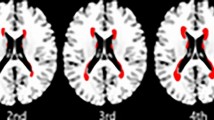

For punctuate deep WMH it is also possible to determine the number and eccentricity of WMH per lobe (see Table 4). In the patient group a total of 594 WMH were located in a frontal location, 46 in a temporal location, 213 in a parietal location and 13 in an occipital location. The distribution across lobes was similar for patients and controls (all p > 0.05). Compared to controls, the patients had a higher eccentricity of WMH in a frontal and parietal location (p < 0.05). These results are graphically visualized in Fig. 3. This figure shows combined mean eccentricity maps of the punctuate deep WMH for the group of patients with T2DM as well as for the control group. This figure illustrates visually that most punctuate deep WMH were in a frontal and parietal location.

Mean eccentricity maps of the punctuate deep WMH. This figure illustrates mean eccentricity maps of the punctuate deep WMH for the group of patients with type 2 diabetes mellitus (T2DM) as well as for the control group. Each colored voxel represents presence of a WMH on that location in at least one participant and the color itself represents the mean eccentricity of all WMH on that location. The colors range from dark blue (low mean eccentricity) to dark red (high mean eccentricity). This figure illustrates that most punctuate deep WMH were in a frontal and parietal location. It also illustrates that in a frontal and parietal location there are visually less dark blue WMH in the patient group compared to the control group. These maps were obtained by automatic registration of the punctuate deep WMH to MNI152 atlas space16. Then, voxels with WMH were assigned to their respective eccentricity value (0 for non-lesion voxels). In both groups the eccentricity values were summed per voxel and divided by the lesion count per voxel, to obtain average eccentricity values per lesion-voxel. Due to minor registration errors some lesions are shown in cortical gray matter on the template image. This had no effect on our statistical analyses, as this template registration was only performed for the current figure.